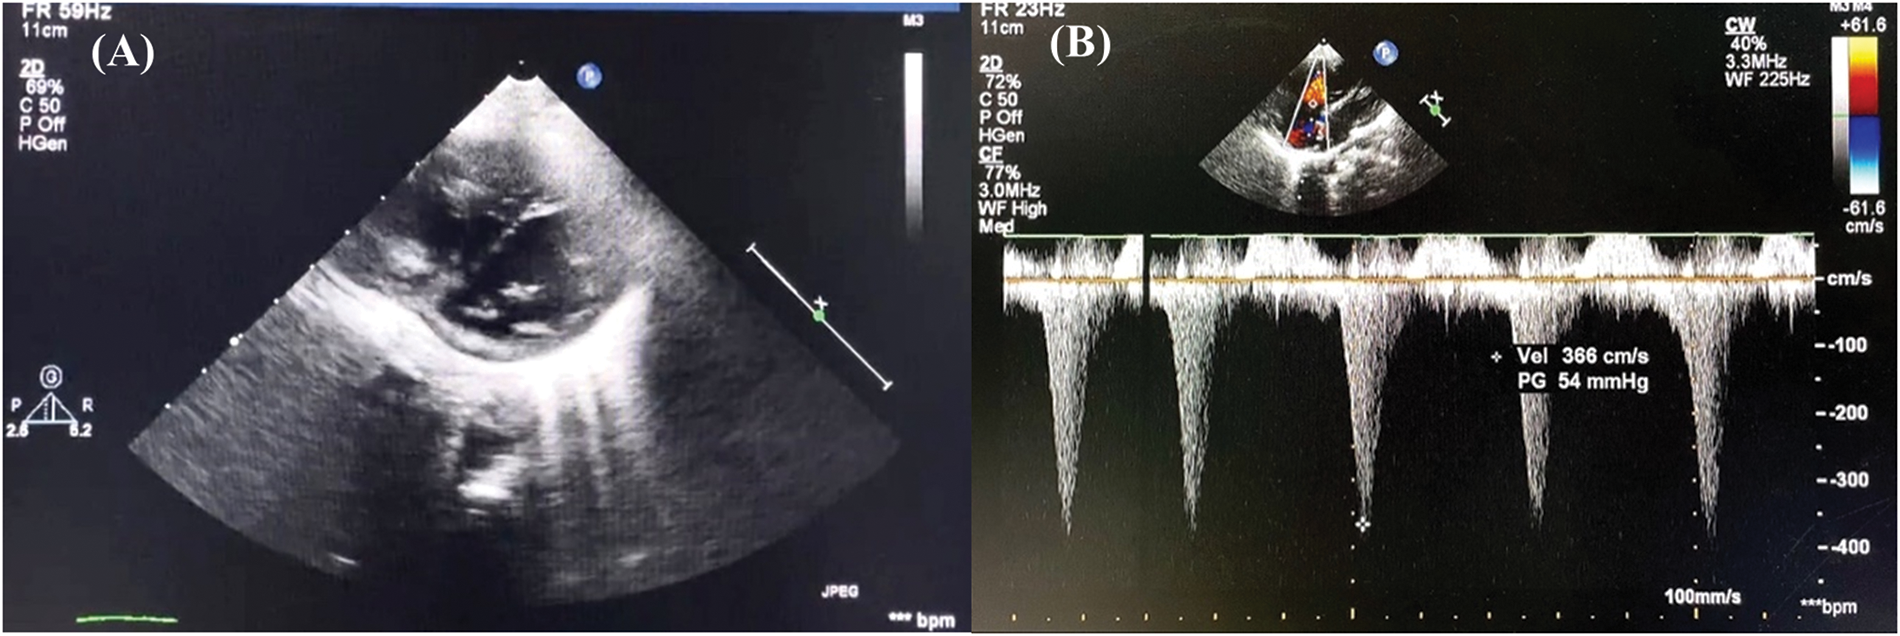

Nitric oxide (NO), as a specific pulmonary artery vasodilator, was immediately given for the patient as the symptoms were suggestive of a pulmonary hypertension crisis. 20 ppm of NO was administered along with a bolus of 500 mL 5% albumin and starting dose of norepinephrine 0.1 mcg/kg/min, resulting in improvement of hemodynamics (BP increased to 92/63 mmHg, CVP reduced to 15 mmHg) and blood gas analysis (pH 7.37, pCO2 33 mmHg, pO2 123 mmHg, SaO2 99%). Gradual weaning of NO therapy was performed until postoperative day (POD) 2, but the patient experienced similar recurrent symptoms. Bedside echocardiography showed a D-shaped left ventricle (LV) and second grade LV diastolic dysfunction [5]. Furthermore, there was right-to-left shunt across the PFO with tricuspid valve gradient of 54 mmHg (Figs. 5A and 5B). No pulmonary regurgitation was observed, and the postoperative right ventricular outflow tract (RVOT) gradient persisted at 16 mmHg. No obstructed flow was seen between the repaired common pulmonary chamber and the left atrium. All these findings confirmed the diagnosis of pulmonary hypertension crisis in a relieved RVOT.

Figure 5: Postoperative day 2 echocardiography in intensive care unit demonstrates (A) left ventricle D-shaped with (B) tricuspid valve gradient 54 mmHg